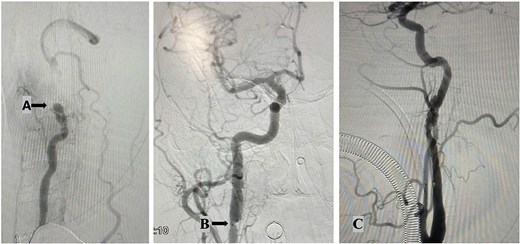

A 48-year-old male with no prior comorbidities was involved in a motorcycle accident, colliding with a car at ~50 mph. He was admitted to the emergency department with a Glasgow Coma Scale score of 14, muscle weakness in all four limbs (grade IV), and severe cervical pain [Visual Analog Scale (VAS) 9]. Initial clinical assessment suggested a significant cervical spine injury with neurological involvement. Radiological evaluation included magnetic resonance imaging (MRI), computed tomography (CT) scan (Fig. 1) and angiography (Fig. 2). MRI revealed a C2–C3 subluxation with right lateral listhesis, where the C2 body was positioned on the right lateral aspect of C3, with locked facets on the left. A fracture line was identified through the C3 body at the right pedicle junction, with splayed bone fragments and slight axial rotation. Sagittal imaging showed anterior listhesis of C2 over C3, loss of cervical lordosis, and segmental kyphosis, with an intact ligamentum flavum and no disc herniation at C2–C3. Angiography confirmed total occlusion of the left vertebral artery and dissection of the right internal carotid artery. The injury was classified as AO C-N3-M4 and Levine Edwards Type III, indicating severe angulation and displacement with facet dislocation.

Angiography findings: Total occlusion of left vertebral artery (A); right internal carotid artery dissection shows an intimal flap and thrombi, along with significant hemodynamic changes. These findings are consistent with arterial dissection. (B); left internal carotid artery dissection shows irregularities in the distal cervical internal carotid artery and the left petrous artery, featuring an intimal flap in the lumen and filling defects from thrombi. These changes result from the dissection (C).